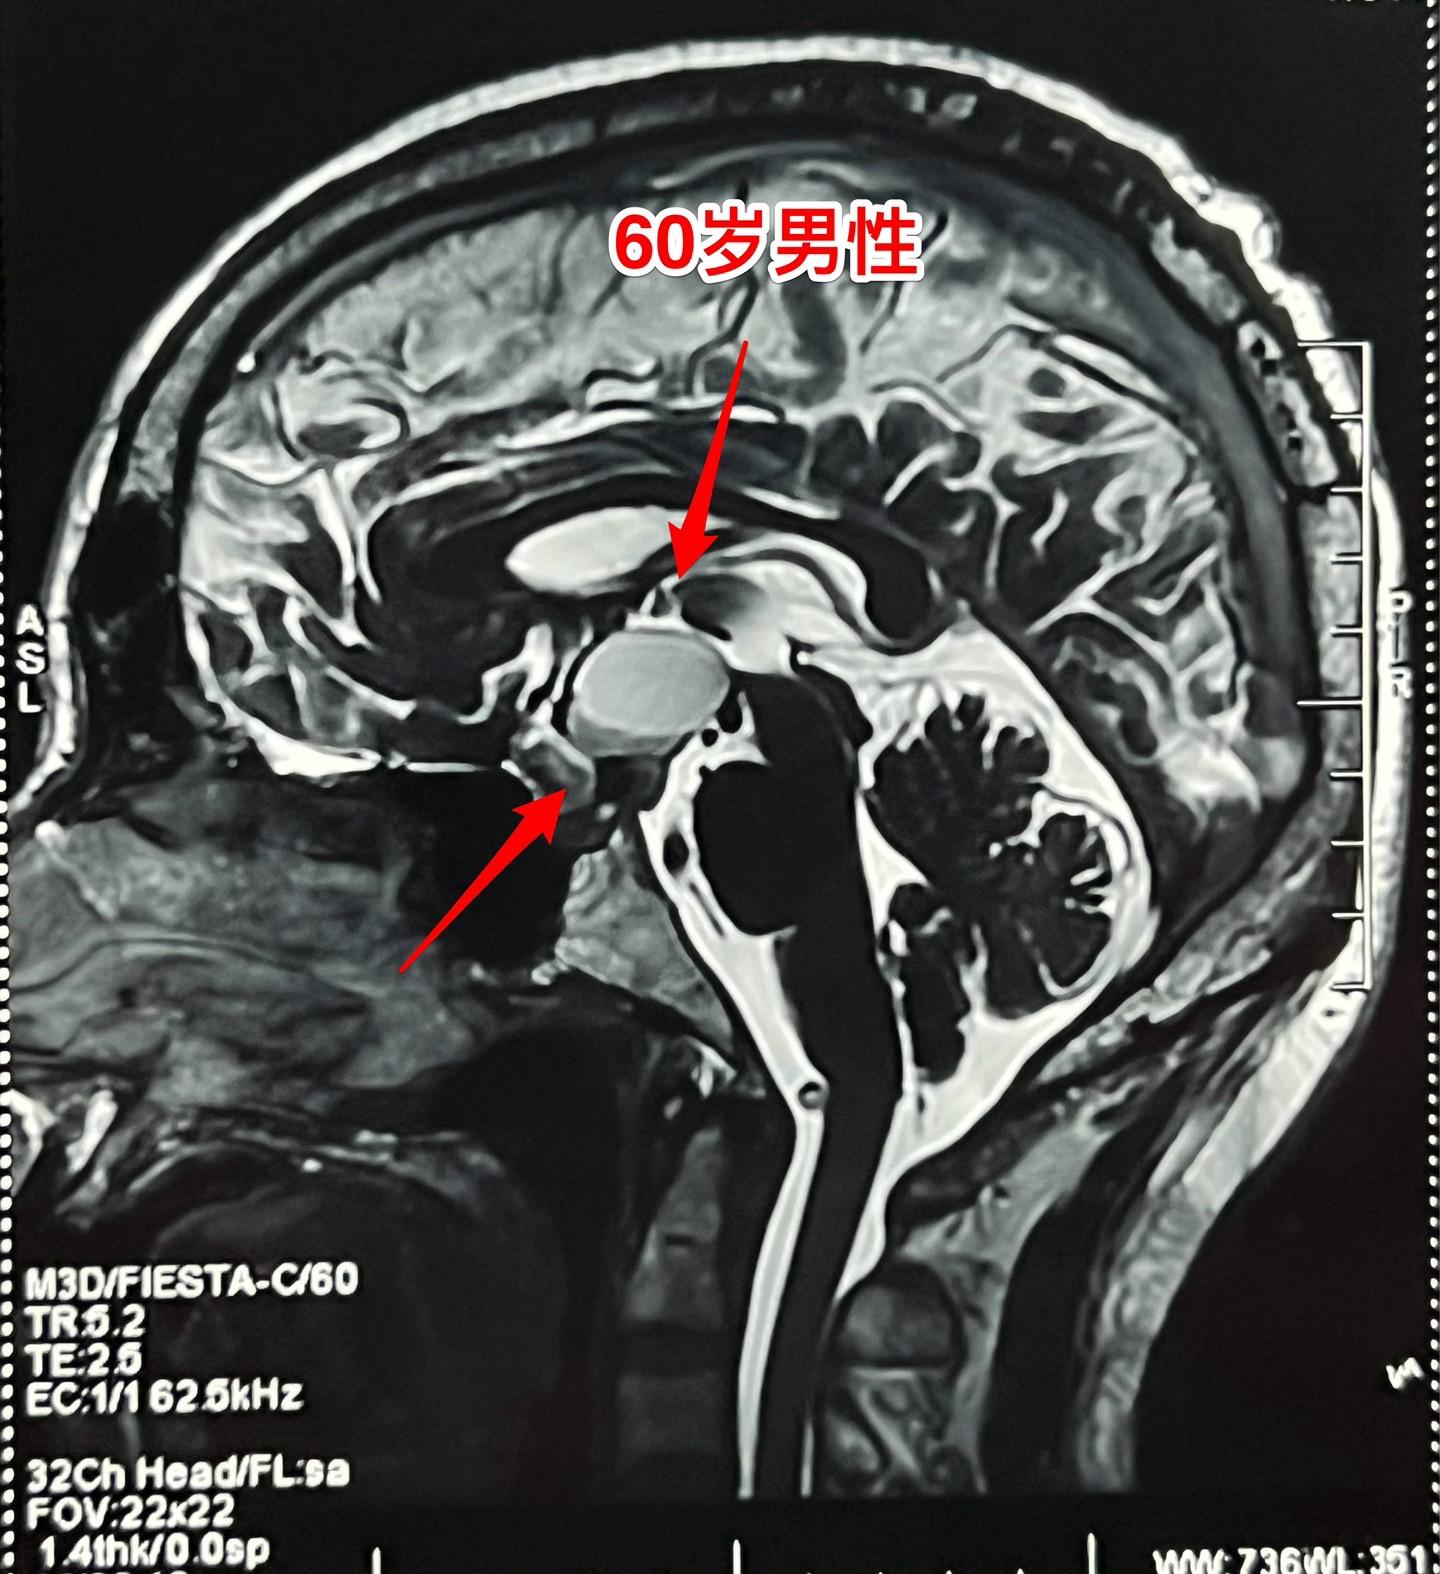

颅咽管瘤与拉克氏囊肿的鉴别不容易。60岁男性,偶然因头痛作体检发现鞍区肿瘤,怀疑为颅咽管瘤。病人无明显的视力下降。肿瘤体积不小了,CT也没有看见钙化。 到底是颅咽管瘤还是拉克氏囊肿? 2024年6月17日作了开颅手术。手术中看见病灶呈囊性,囊壁边界清楚,内有胆固醇结晶体,其周围脑实质有黄染。垂体柄得到保留。 手术后病理报告为:拉克氏囊肿。颅咽管瘤拉克氏囊肿